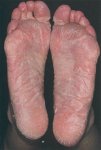

Трещины кожиТрещины кожи. Народная медицина рекомендует следующие средства: - Лапчатка прямостоячая (калган). Для... Трещины кожиТрещины кожи. Народная медицина рекомендует следующие средства: - Лапчатка прямостоячая (калган). Для...